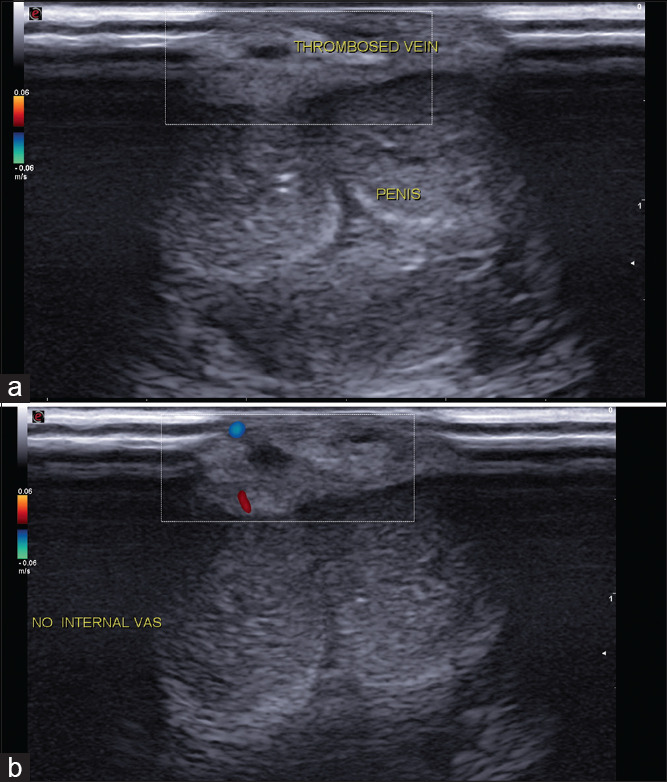

Penile Mondor's disease co-occurring with sclerosing lymphangitis: A double whammy.